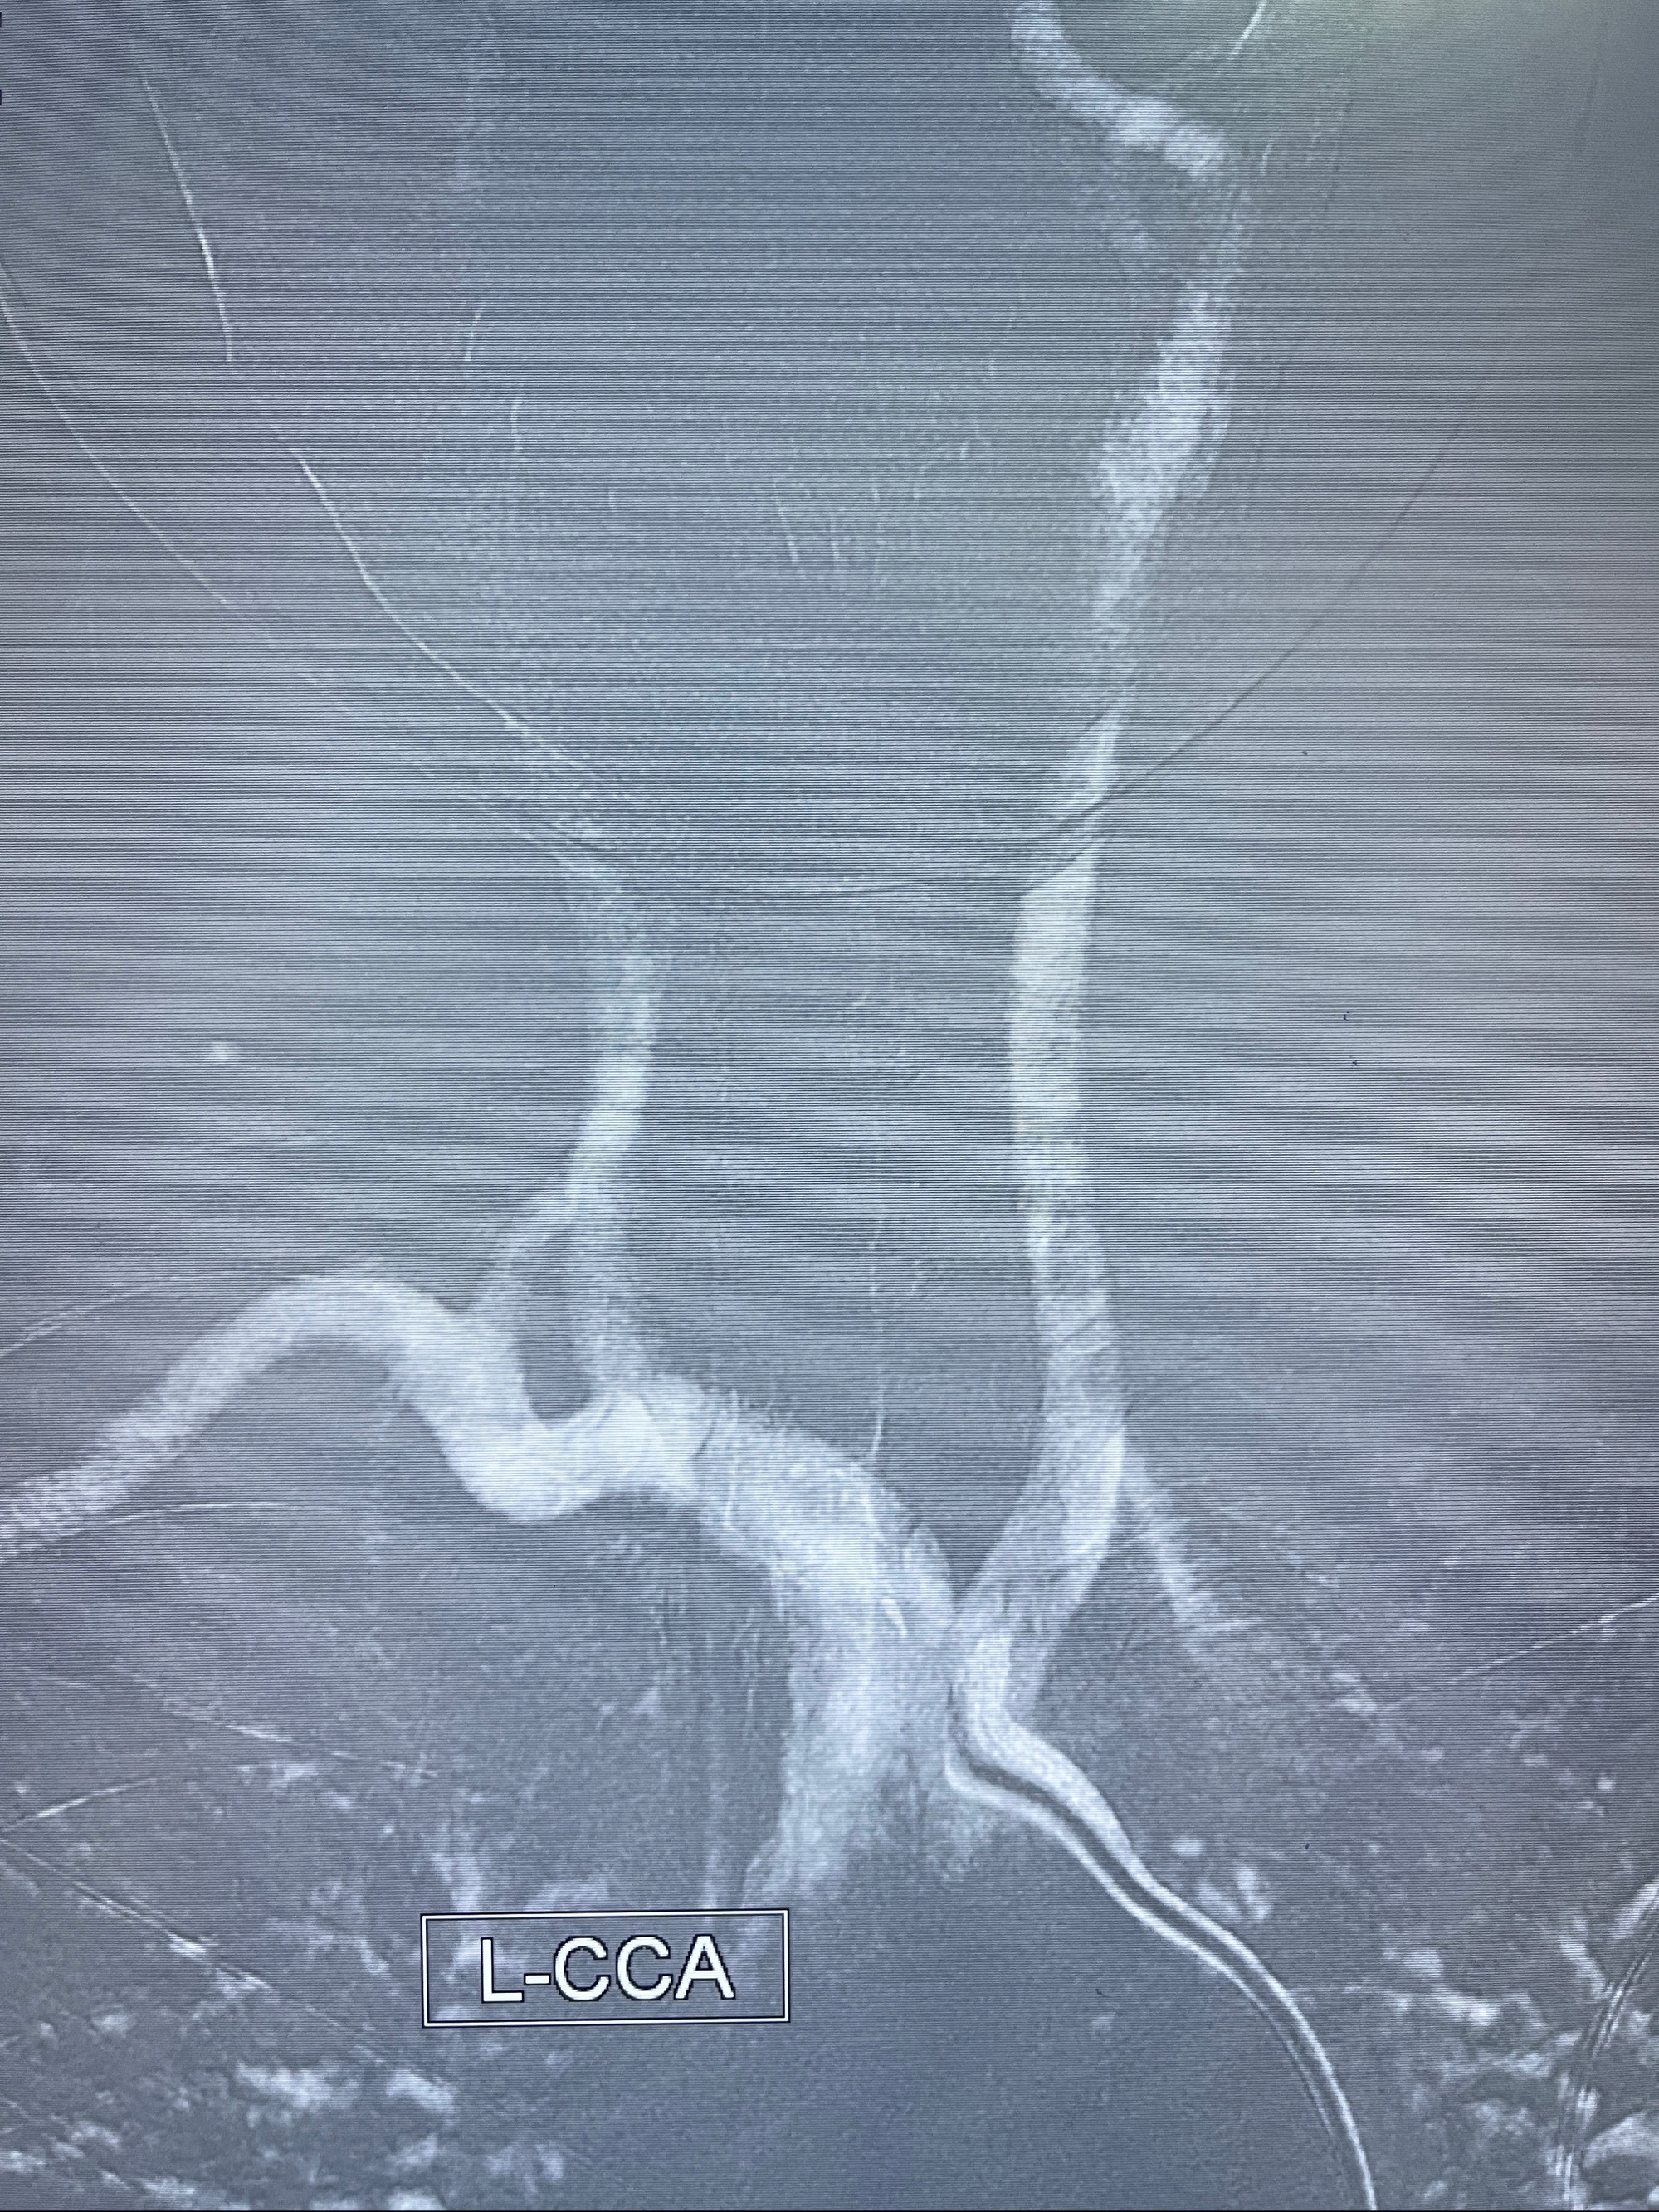

2023-08-14DSA:

左侧大脑中动脉动脉瘤,约2.6-2.8-3.4-2mm大小(瘤颈部、瘤体部、瘤高)

1.左侧大脑中动脉动脉瘤,约2.6-2.8-3.4-2mm大小(瘤颈部、瘤体部、瘤高)

2.外科手术夹闭or介入支架辅助栓塞